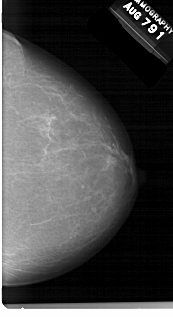

A_1541_1.RIGHT_CC

RIGHT_CC LINES 6016 PIXELS_PER_LINE 3286 BITS_PER_PIXEL 12 RESOLUTION 43.5 NON_OVERLAY